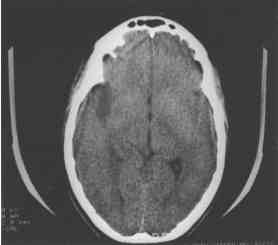

Figura 2.:

Area hipodensa temporal derecha secundaria a encefalitis herpética